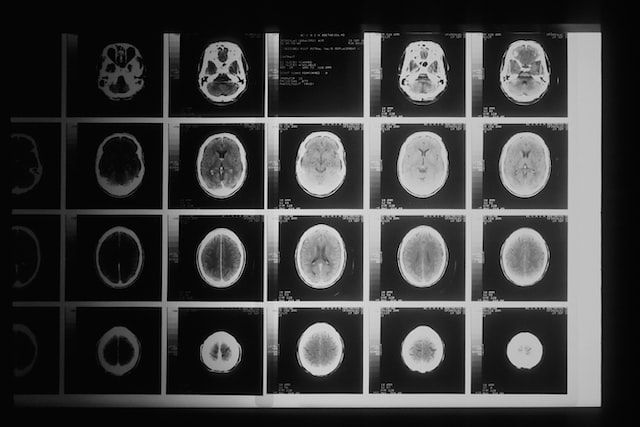

Инсульт в составе сосудистых заболеваний занимает в Якутии второе место по распространенности после онкологии, а по всему миру уже несколько лет сохраняет лидирующие позиции по смертности и инвалидизации. Заведующая неврологическим отделением для больных с острыми нарушениями кровообращения регионального сосудистого центра при республиканской больнице № 2 Саргылана Шарина рассказала ЯСИА, как уберечься инсульта, кто входит в группу риска и что предпринимают врачи для снижения тяжелых последствий болезни.

«В районных медучреждениях зачастую нет профильных специалистов, но мы решили этот вопрос с помощью телемедицины. Врачи из нашего отделения в РБ № 2 консультируют своих коллег через видеосвязь, и в этом году мы одними из первых по всей стране запустим практику телетромболизиса. Врачи из Якутска смогут вести пациентов удаленно. Подобный подход будет применяться во всех районных больницах, где установлена компьютерный томограф», — отмечает Саргылана Шарина.